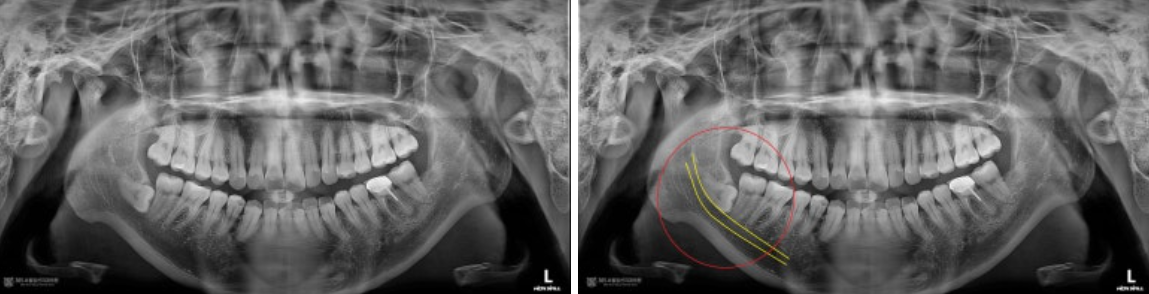

촬영일시 : 2024.09.06. 사진상에서 좌측(구강내 우측) 아래쪽에 아주 깊게 매복된 사랑니가 관찰됩니다. 노란색으로 표시된 신경관과 수평으로 완전히 접하고 있는 모습을 볼 수 있으며, 발치 난이도가 매우 높아 보입니다. 신경손상이 없이 안전하게 발치해야겠습니다.

촬영일시 : 2024.09.06. 대략 15분 정도 지나서 발치를 완료한 후 남은 치아조각이 있는지 확인차 촬영한 작은 엑스레이 사진입니다. 남은 치아 조각 없이 깨끗하고 안전하게 발치된 모습을 볼 수 있습니다 ㅎㅎ 촬영일시 : 2024.09.06. 전체 엑스레이 사진입니다. 깔끔하게 발치된 모습을 볼 수 있습니다 ㅎㅎ 전체 엑스레이 사진입니다. 깔끔하게 발치된 모습을 볼 수 있습니다 ㅎㅎ 난이도 높은 매복 사랑니 발치 또한 자신있게 치료하는 주안역사랑니치과 365서울앞선치과였습니다 ㅎㅎ [ 치료기간: 2024년 9월 6일 ] ※ 365서울앞선치과의원의 모든 포스팅은 각 진료과 의료진이 직접 작성합니다. 365서울앞선치과의원 블로그의 임상 케이스 게시물은 환자분께 의학적으로 정확하고 상세한 정보를 드리기 위해 각 진료과 의료진이 직접 작성하며, 모든 증례 사진은 본원 의료진이 직접 시술한 증례를 촬영한 것으로, 의료법 제23조, 제56조에 의거하며 환자분의 동의를 얻어 포스팅에 사용하였습니다. 또한 해당 케이스는 본 환자분의 치료 결과이며, 환자 상태에 따라 치료의 결과는 달라질 수 있습니다. |